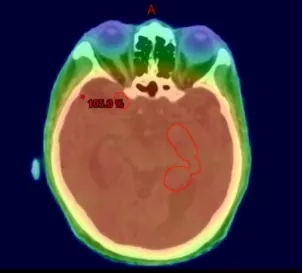

全脑照射,正常脑组织承受的辐射剂量跟肿瘤一样

VMAT容积旋转调强放疗,在同一个面上对肿瘤进行360°全方位照射

360°照射示意图